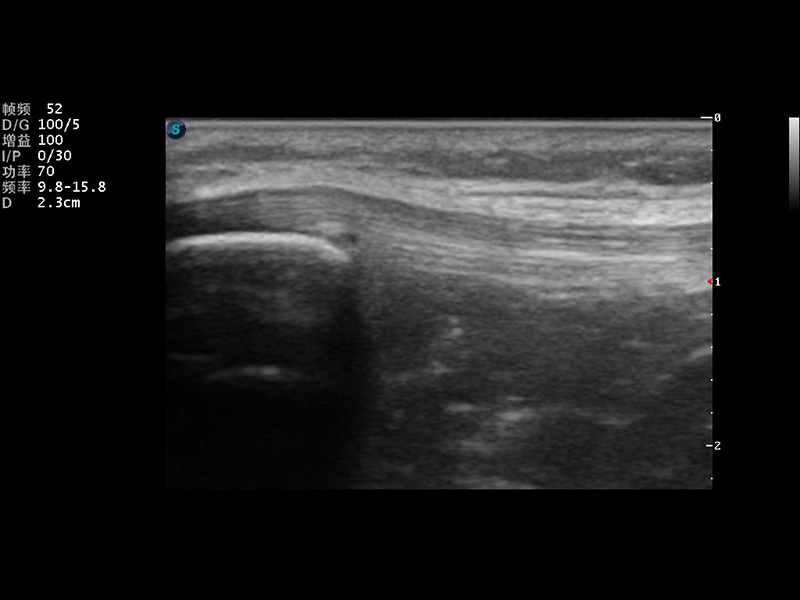

S9便携式彩色多普勒超声诊断仪是玖鼎集团研发的高端便携彩超设备,外观设计新颖、产品性能卓越。S9在便携超声领域采用了突破传统的触摸屏交互设计,并以先进的软件硬件技术和设计理念,为您带来清晰的图像质量、稳定的工作性能和便捷的操作体验。

成像技术